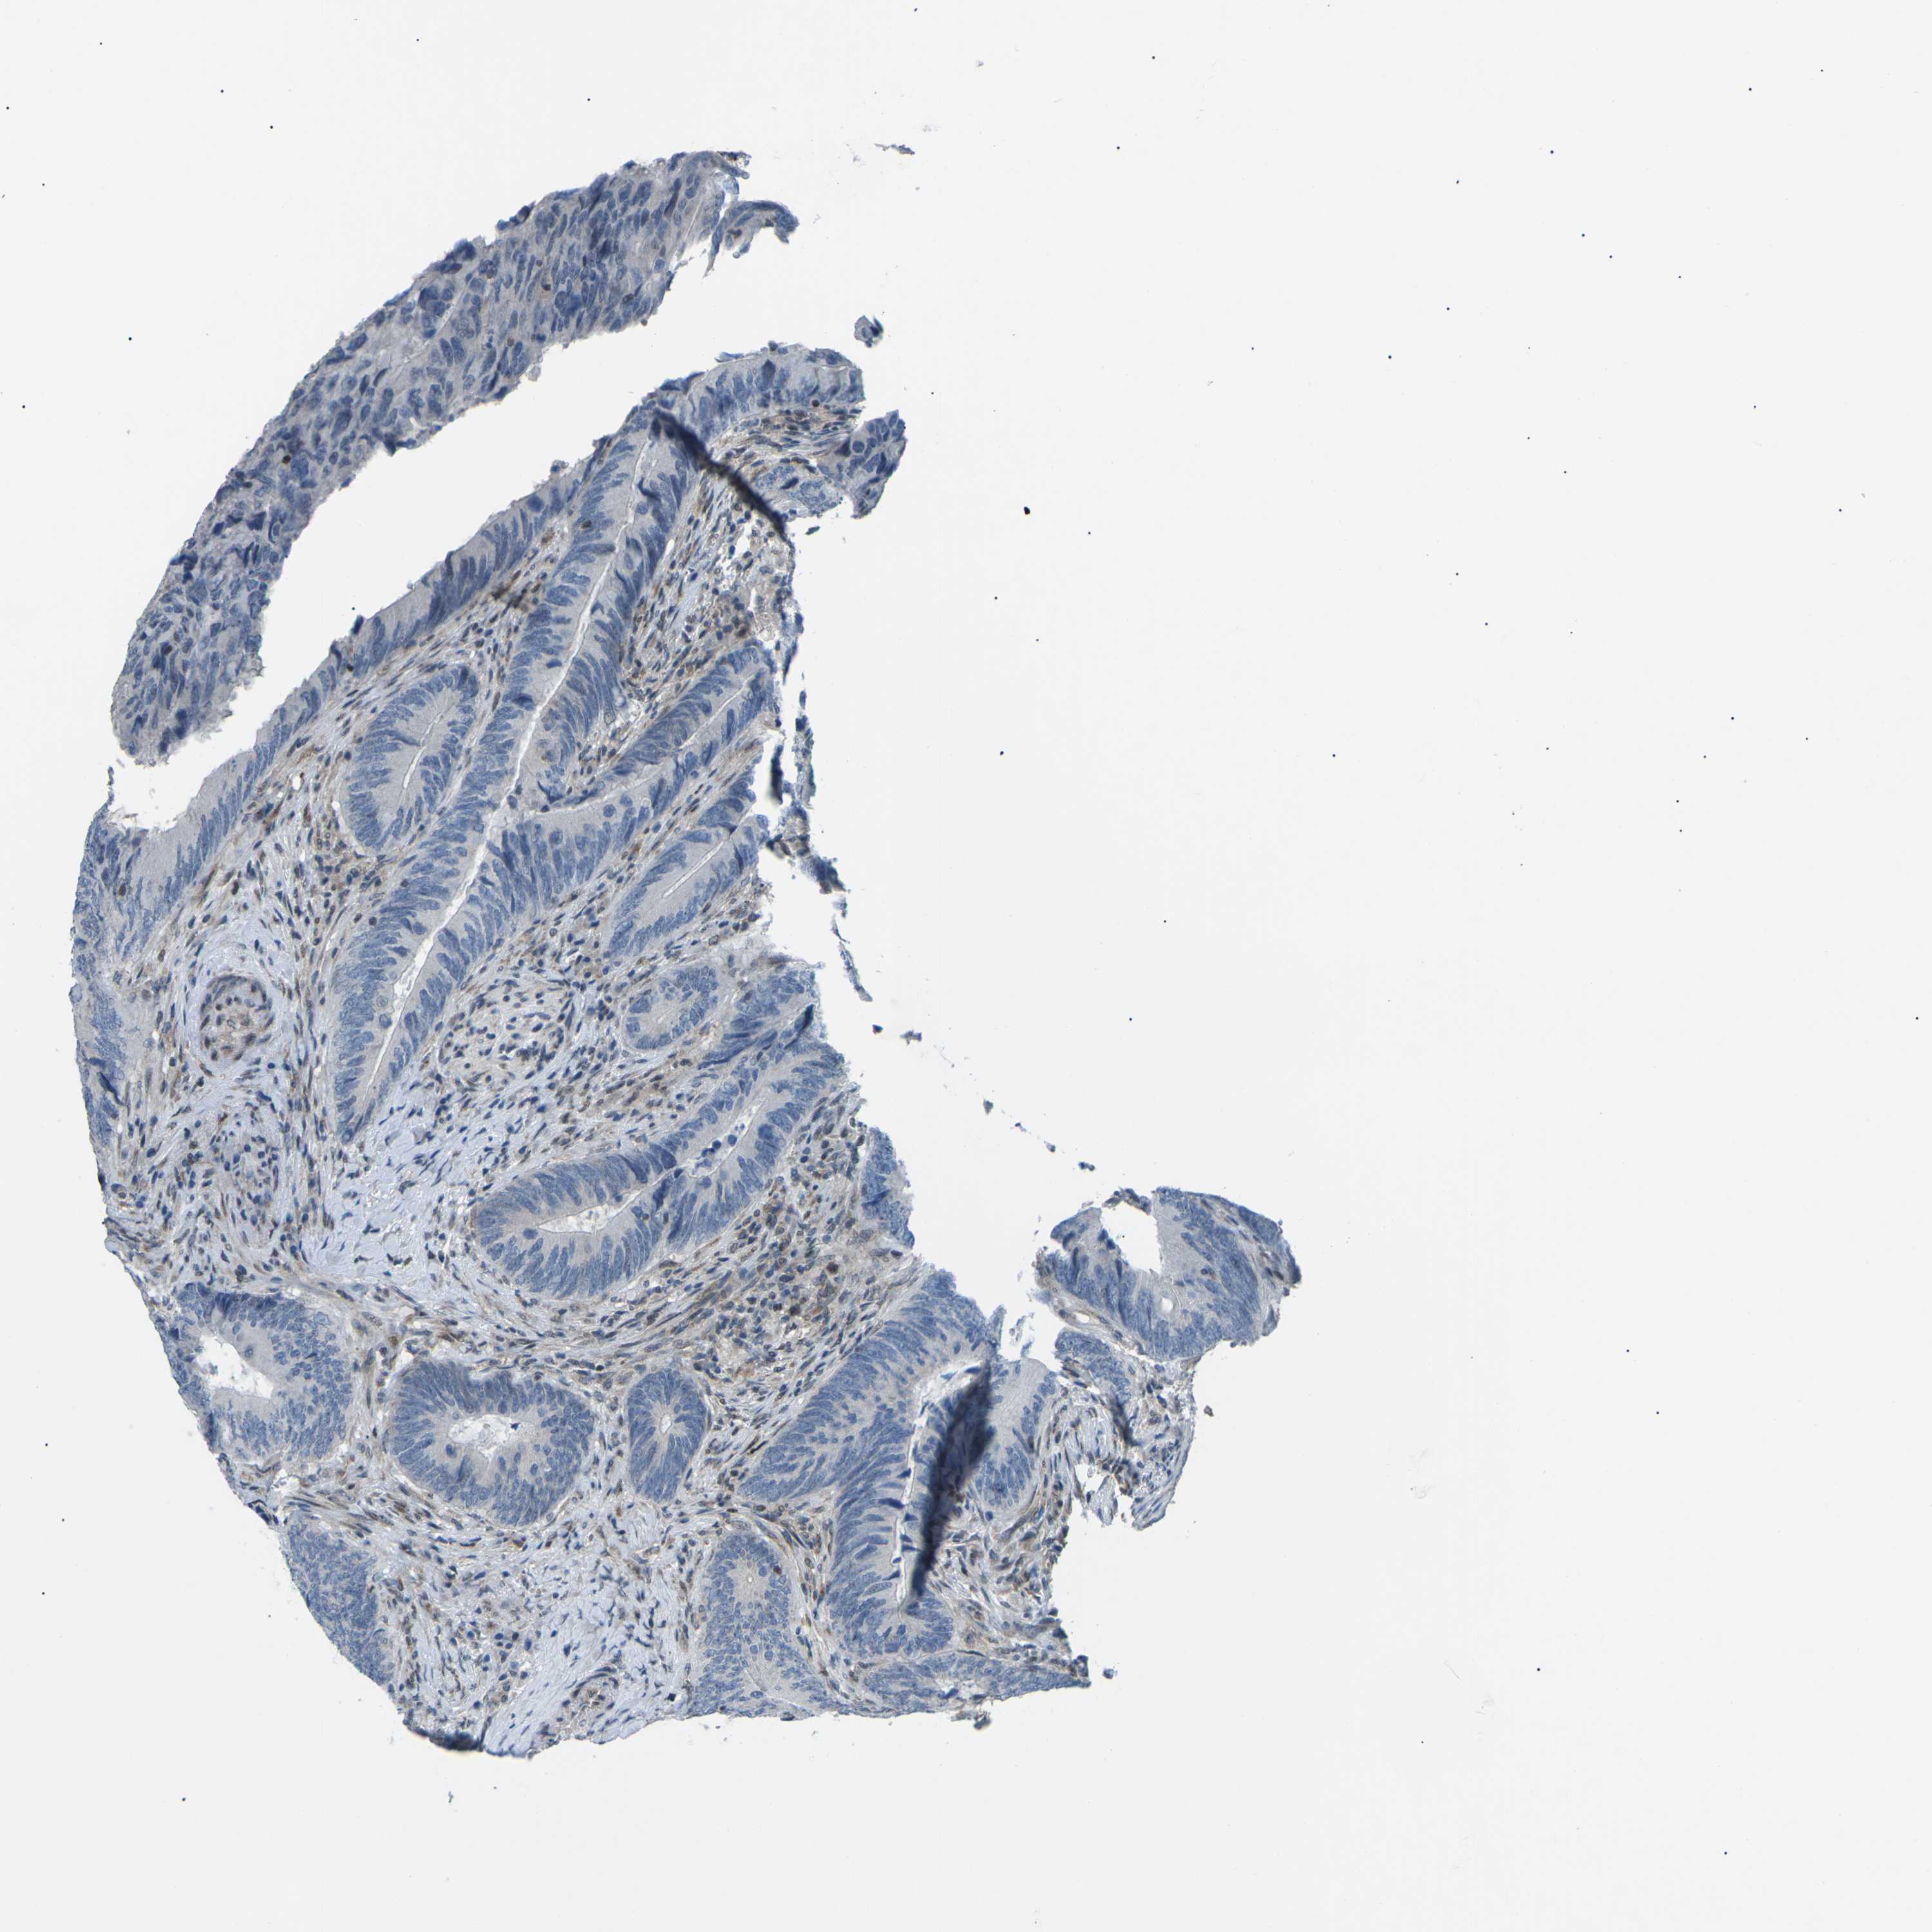

CANCER COLORECTAL CANCER Show tissue menu

Colorectal cancer

Human cancer

Colon adenocarcinoma